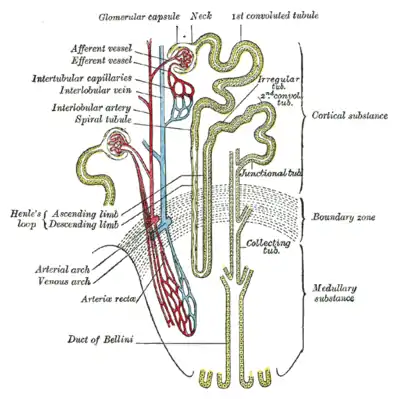

Scheme of renal tubule and its vascular supply. (1st convoluted tubule labeled at center top.) | |

The proximal tubule is the segment of the nephron in kidneys which begins from the renal pole of the Bowman's capsule to the beginning of loop of Henle. At this location, the glomerular parietal epithelial cells (PECs) lining bowman’s capsule abruptly transition to proximal tubule epithelial cells (PTECs). The proximal tubule can be further classified into the proximal convoluted tubule (PCT) and the proximal straight tubule (PST).

In relation to the morphology of the kidney as a whole, the convoluted segments of the proximal tubules are confined entirely to the renal cortex.

Straight segments descend into the outer medulla. They terminate at a remarkably uniform level and it is their line of termination that establishes the boundary between the inner and outer stripes of the outer zone of the renal medulla.